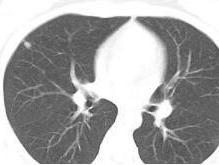

支原体肺炎患者胸部X线检查变化很大,病变可很轻微,也可很广泛。体征轻微而胸片阴影显著,是本病特征之一。血常规检查白细胞高低不一,大多正常,有时偏高。

支原体肺炎的临床表现和胸部X线检查并不具特征性,单凭临床表现和胸部X线检查无法做出诊断。若要明确诊断,需要进行病原体的检测。国内支原体肺炎的诊断主要依靠血清学检测。